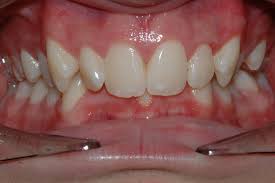

دراین نوع ناهنجاری در اکثر موارد دندان های فک بالا و پایین همپوشانی بیش از حدی دارند و در بعضی موارد شدید ممکن است دندان های یک فک بیمار به دلیل پوشش بیش از حد توسط دندان های فک مقابل ممکن است اصلا دیده نشوند.

همپوشانی بیش از حد دندان ها معمولاً در ناحیه دندان های جلویی (دیپ بایت قدامی) و در موارد نادری در ناحیه دندان های خلفی مشاهده می شود.

همپوشانی بیش از حد دندانها نیز ممکن است همراه با سایر ناهنجاریها

بخصوص ناهنجاری کلاس ۲ دیده شود. در مواقعی که فک پایین کوچک

و عقب تر قرار دارد ممکن است دندانهای فک پایین تا ایجاد تماس با دندانهای

بالا رویش بیابند که منجر به افزایش همپوشانی دندانها شود.در موارد بسیار

شدید حتی ممکن است دندانهای فک پایین بقدری رویش بیابند که حتی با کام

تماس پیدا کنند و حتی گاها ممکن است اصلا درحین بستن دندانها دندانهای فک

پایین دیده نشوند.